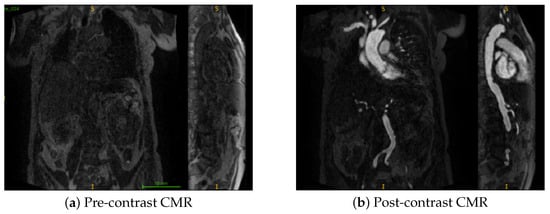

Transcatheter aortic valve implantation (TAVI) is a minimally invasive procedure for treating severe aortic stenosis, where optimal vascular access route selection is critical to reduce complications. It requires careful selection of the iliac artery with the most favourable anatomy, specifically, one with the [...] Read more.

Transcatheter aortic valve implantation (TAVI) is a minimally invasive procedure for treating severe aortic stenosis, where optimal vascular access route selection is critical to reduce complications. It requires careful selection of the iliac artery with the most favourable anatomy, specifically, one with the largest diameters and no segments narrower than 5 mm. This process is time-consuming when carried out manually. We present an active learning-based segmentation framework for contrast-enhanced Cardiac Magnetic Resonance (CMR) data, guided by probabilistic uncertainty and pseudo-labelling, enabling efficient segmentation with minimal manual annotation. The segmentations are then fed into an automated pipeline for diameter quantification, achieving a Dice score of 0.912 and a mean absolute percentage error (MAPE) of 4.92%. An ablation study using pre- and post-contrast CMR showed superior performance with post-contrast data only. Overall, the pipeline provides accurate segmentation and detailed diameter profiles of the aorto-iliac route, helping the assessment of the access route. Full article

Show Figures